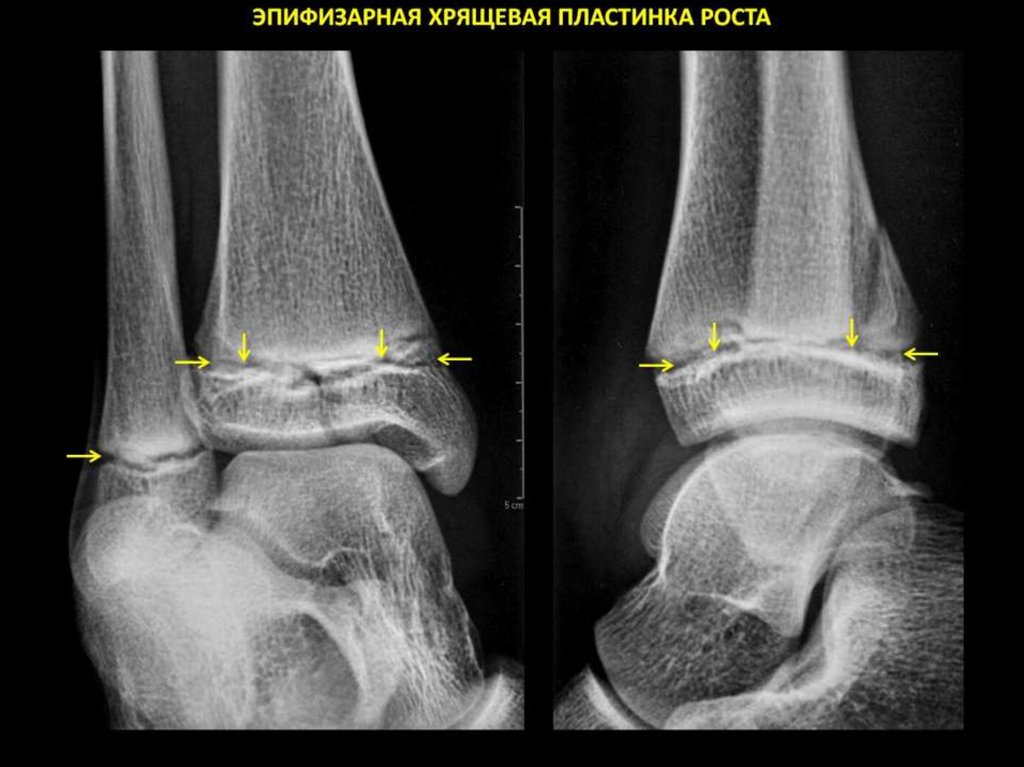

Функциональная анатомия и морфогенез костной ткани.

Компактная и губчатая кости. Адаптационный морфогенез костной ткани. Костная

система. Костная ткань. Виды костей. Кость как орган. Остеон. Механизмы

ремоделирования костной ткани и кости.